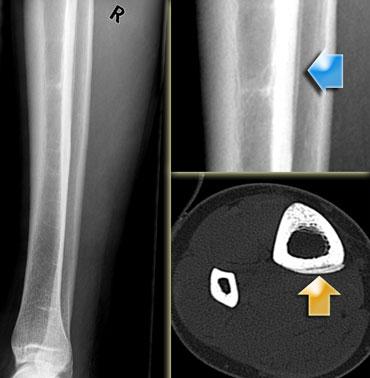

X-quang và CT cho thấy đường nứt tại điểm bám của cơ gấp các ngón dài. Hình ảnh do Bác sĩ Wuisman cung cấp (3)

Hình bên trái là một vận động viên chạy bộ 24 tuổi với triệu chứng đau cẳng chân kéo dài bốn tháng.

Ban đầu cơn đau chỉ xuất hiện khi chạy, nhưng cuối cùng đau cả khi nghỉ ngơi.

X-quang ban đầu được đọc là bình thường.

Xạ hình xương (không trình bày) cho thấy vùng tăng hoạt tính khu trú.

CT được thực hiện để phân tích thêm và phát hiện đường nứt theo chiều dọc tại điểm bám của cơ gấp các ngón dài.

Bệnh nhân được điều trị bằng sáu tuần nghỉ ngơi,

sau đó tăng dần cường độ tập luyện.

Hình bên trái là một nam giới 50 tuổi, vốn có lối sống ít vận động.

Ông tham gia một cuộc thi đi bộ 10 dặm mà không có bất kỳ sự chuẩn bị tập luyện nào trước đó.

Cơn đau ở cẳng chân xuất hiện từ từ và cuối cùng ông không thể tiếp tục đi bộ.

X-quang cho thấy gãy xương do stress ở đầu dưới xương chày.

Vận động quá mức trong thời gian ngắn là nguyên nhân thường gặp của gãy xương do stress.